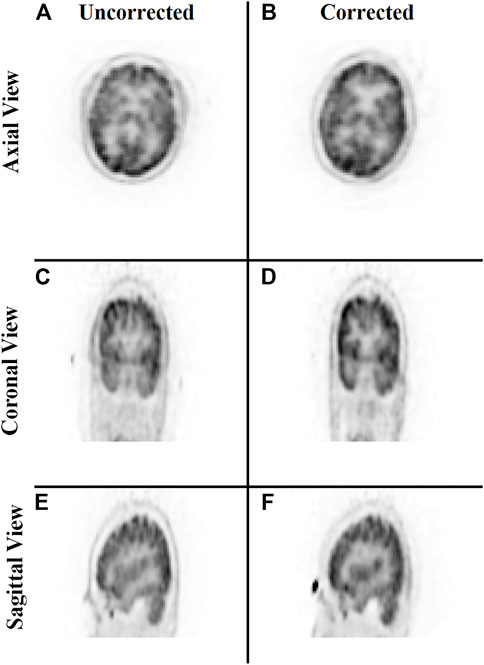

Lastly, a study was conducted to evaluate the correction of the original raw listmode data by repositioning the LORs with the transformation parameters estimated by the trained neural network. Figure 9 provides a qualitative comparison of the uncorrected and motion-corrected image volumes reconstructed from the repositioned listmode data. Motion-corrected image volume achieved sharper details compared to the uncorrected data.

FIGURE 9. Qualitative comparison of the neural network performance in motion correction by remapping raw listmode data. Rows from top to bottom show the sum of the three frames without any correction (A,C,E) and correction using the deep learning approach (B,D,F), respectively, in the axial, coronal, and sagittal view.